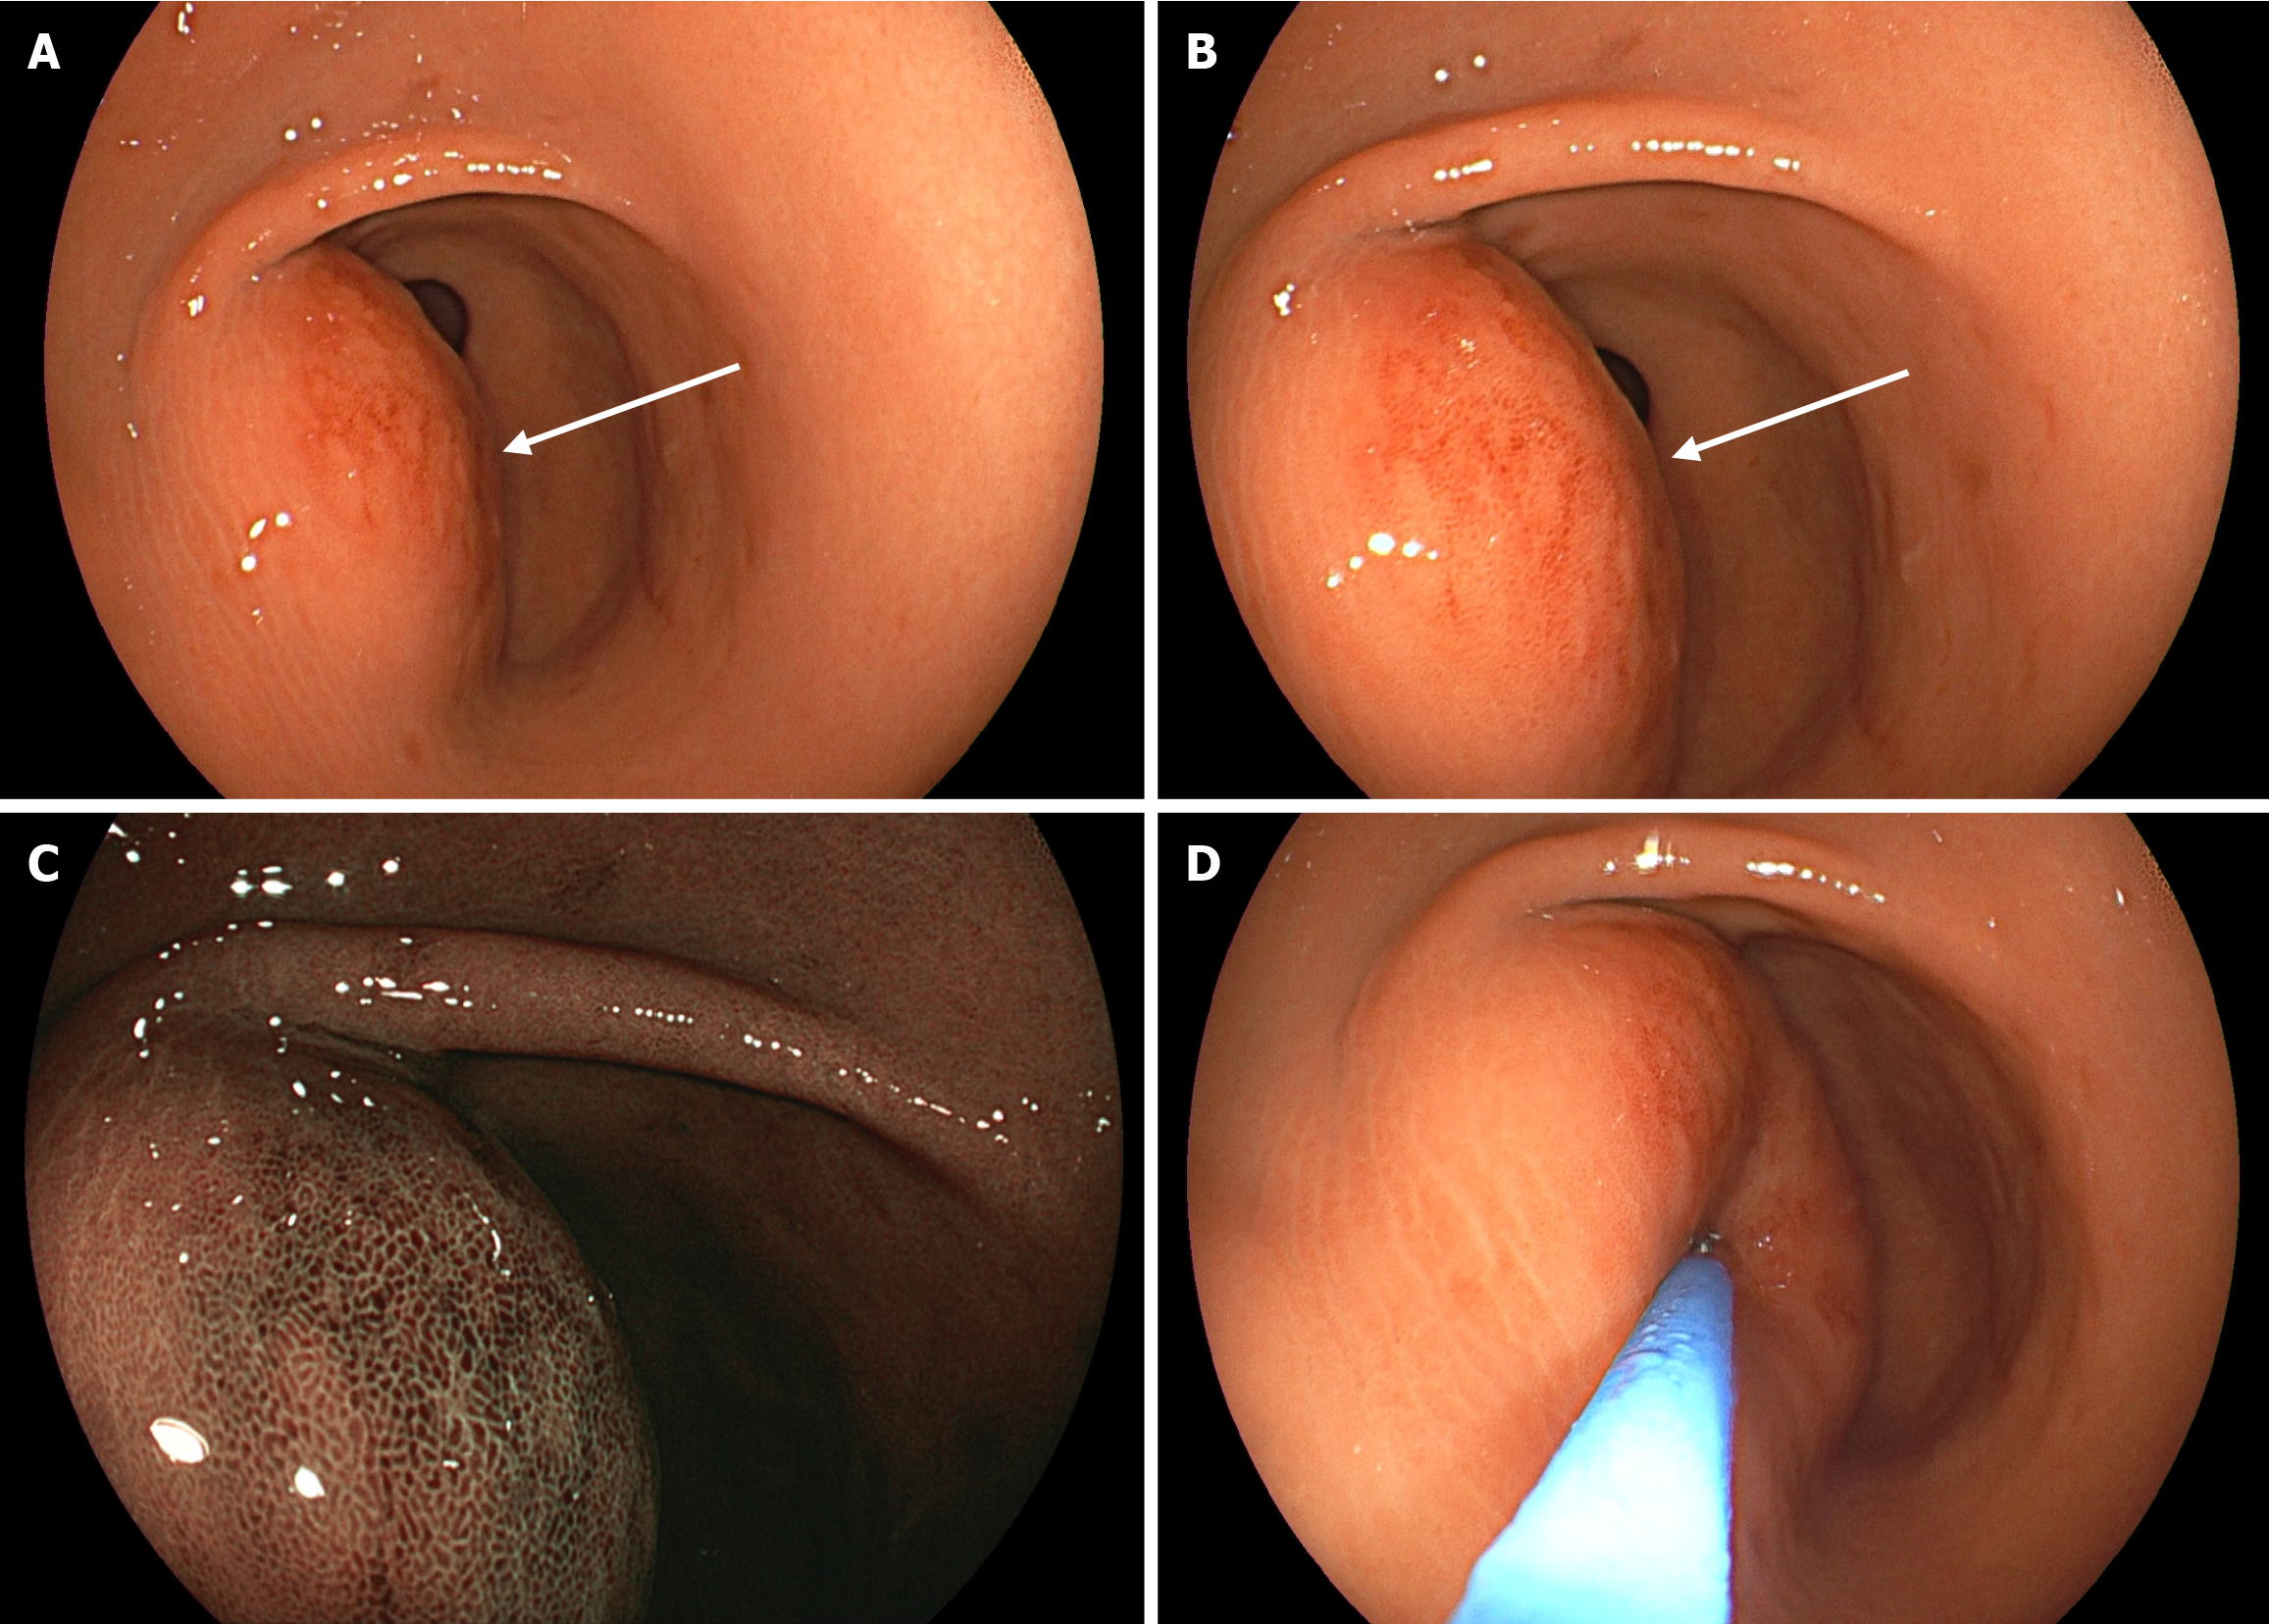

Figure 2 Contrast-enhanced computed tomography images.

A: Plain computed tomography showed significant thickening of the anterior wall of the gastric body and antrum with low-density areas; B: The mucosal line appeared continuous, with the lesion in the submucosa surrounded by patchy edema; C: In the arterial phase, multiple submucosal cystic lesions of varying sizes were visible in the anterior wall of the gastric antrum, with ring-like enhancement of the cyst walls; D: In the venous phase, the cyst walls exhibited persistent enhancement; in contrast, the cyst contents remained non-enhancing.